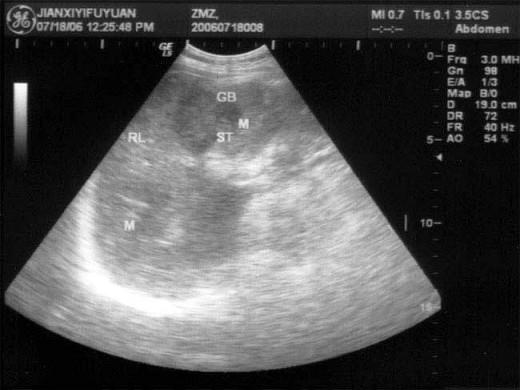

问题 患者男46岁,既往有胆囊结石病史,上腹部疼痛不适年余,加重1个月,皮肤、巩膜轻度黄染,B超检查如图所示,根据超声声像图,诊断为?(?)

选项 A.胆囊结石并胆囊炎,肝血管瘤 B.胆囊结石并胆汁淤积,肝血管瘤 C.胆囊结石并胆囊癌,肝转移性癌 D.胆囊结石并肝癌 E.胆囊结石并胆息肉,肝转移性癌

答案 C